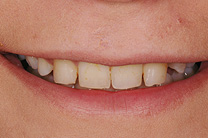

Brücken

Muss ein Zahn entfernt werden, hinterlässt er eine Lücke. Diese kann mit einer Brücke wieder geschlossen werden. Eine Brücke ist ein zahngetragener, fest zementierter Zahnersatz. Sie besteht in der Regel aus zwei Kronen und einem oder mehreren Zwischengliedern. Bei einer bestehenden Lücke muss immer zwischen einer Brückenversorgung und einer Implantatlösung gut abgeklärt und abgewogen werden.

Fallbeispiel

Zum Vergrössern klicken